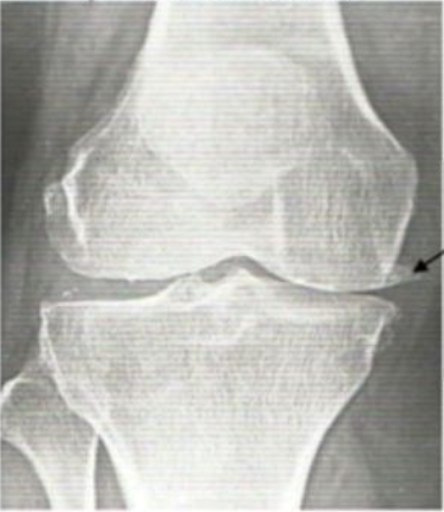

Would you like your knees to go from this: